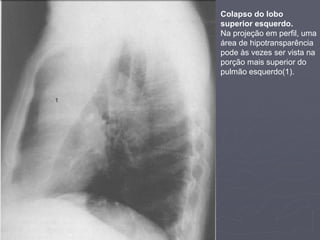

Colapso do lobo

superior esquerdo.

Na projeção em perfil, uma

área de hipotransparência

pode às vezes ser vista na

porção mais superior do

pulmão esquerdo(1).